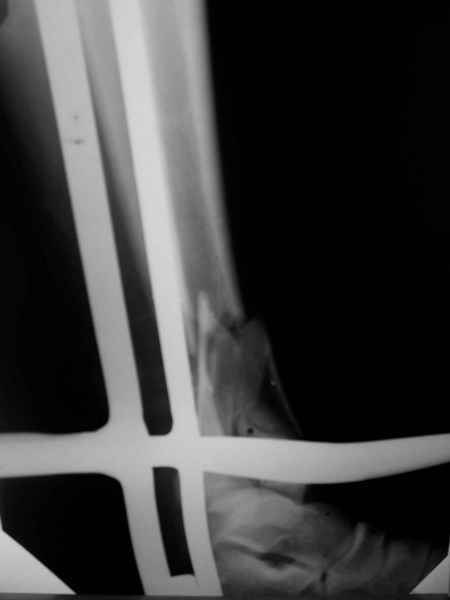

Открытый оскольчатый перелом н/3 голени.

Здравствуйте, коллеги! 16/10/06 г. В отделение поступила больная с производственной травмой - Открытый оскольчатый перелом метафиза и метадиафиза обеих костей правой голени со смещением отлоков.

Здравствуйте коллеги! В данной ситуации я полностью согласен с мнением Александра Николаевича! Практически любой внутрисуставной(тем более приведенный на снимках) перелом требует открытой репозиции.Судя по приведенным рентгенограммам, в области дистального тибио-фибулярного сочленения имеется "минус" ткань на tibia, которая может потребовать костной пластики.Метод фиксации любой,главное ранние движения в суставе. С уважением Руслан Ш.

К слову, тема этого обсуждения обозначена неточно, тут перелом дистального суставного конца типа 43-C, а не "открытый оскольчатый перелом н/3 голени", т.е. диафизарный, 42-.

Действительно, речь идет о сложном внутрисуставном, да еще и открытом переломе 43С.3.

1. Представленные рентгенограммы во-превых плохого качества (ну да ерунда), а во-вторых (самое главное) - в нестандартных проекциях. Невозможно оценить количество и положение фрагментов суставной поврехности. Собственно это делает обсуждение бессмысленным. Мы обсуждаем не конкретный случай, а вообще...